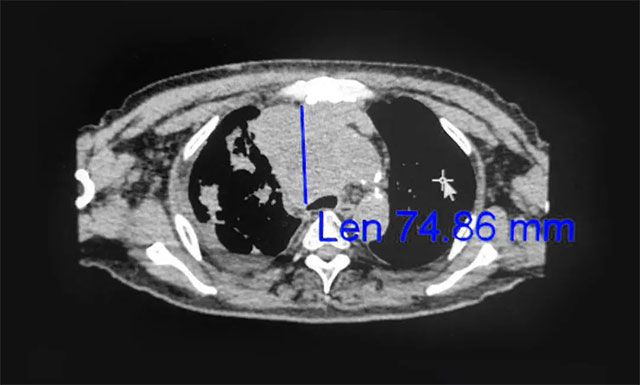

▲ 放療后

對于肺癌的治療方法,王曉東主任介紹說,其主要有:手術治療、化學治療、放射治療等綜合治療,才能取得比較好的效果。而卞先生的病灶位置不是很理想,所以治療時要特別注意。如今,卞先生有現(xiàn)在的治療效果已很不錯了。醫(yī)生治療是一方面,患者的心態(tài)也很重要!要有信心,才能有希望!